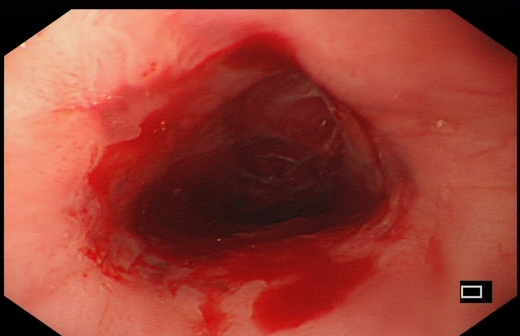

扩张治疗后

扩张后明显通畅